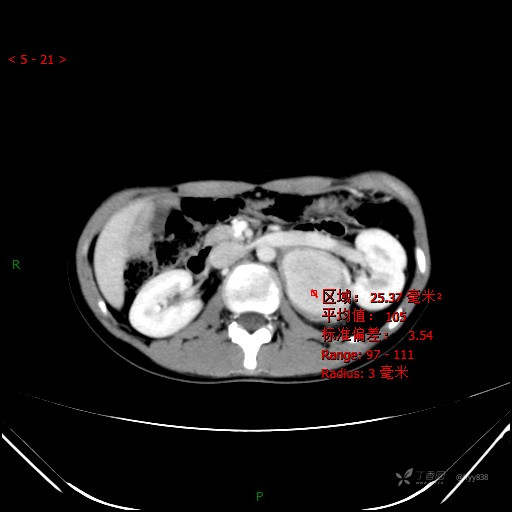

CT值